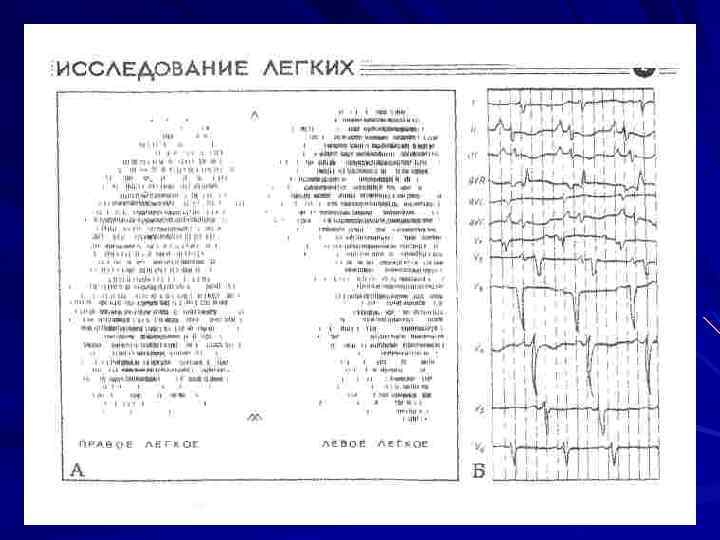

-Функция внешнего дыхания (нормативы): ЖЕЛ: муж. – 4 – 5 л. Жен. – 3 – 4 л. ОФВ 1: муж. – 3 – 4 л. Жен. – 2 – 3 л. Индекс Тиффно: ОФВ 1/ЖЕЛ х 100 (70 – 85%). МВЛ: муж. – 100 – 125 л мин. жен. - 80 – 100 л мин. - Сканирование легких (радиоизотопное исследование).